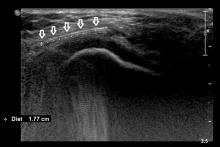

Przypadek 52: 6-letnia dziewczynka zgłosiła się do IP po przypadkowym wbiciu się igły krawieckiej w tkanki bocznej części kolana lewego.

Rozpoznanie: W badaniu usg uwidoczniono linijne ciało obce - igłę (strzałki) - w tkankach miękkich bocznej części kolana.